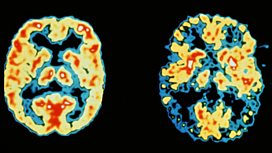

![]() - In our medical special today we ask: what are the first signs of Dementia?